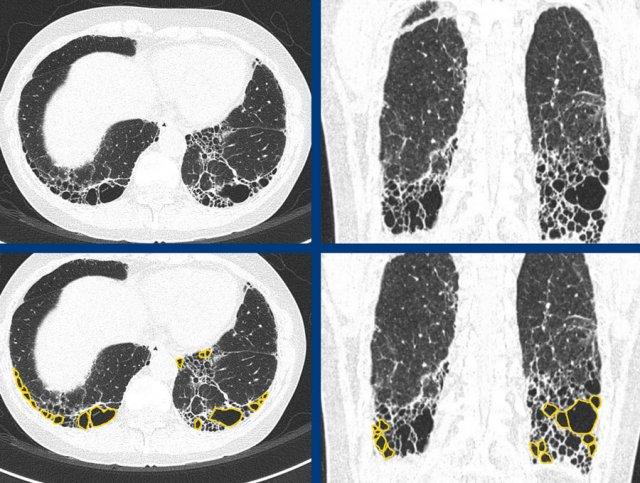

Typical fibrotic hypersensitivity pneumonitis showing diffuse non-basal dominant (A), peribronchial orientated ground-glass and mild fibrotic changes with mosaicism (A and B), and expiratory air trapping (C).

Hypersensitivity pneumonitis

HP mạn tính xơ hóa điển hình được đặc trưng bởi xơ hóa quanh phế quản với các mức độ kính mờ khác nhau và suy giảm khảm rõ rệt do sự bảo tồn của các tiểu thùy thứ cấp.

Bẫy khí thì thở ra do tắc nghẽn đường thở nhỏ là một dấu hiệu đặc trưng.

Xơ

hóa có thể có phân bố ngẫu nhiên hoặc lan tỏa, hoặc ưu thế ở vùng phổi giữa hoặc trên với tương đối ít tổn thương ở vùng đáy phổi.